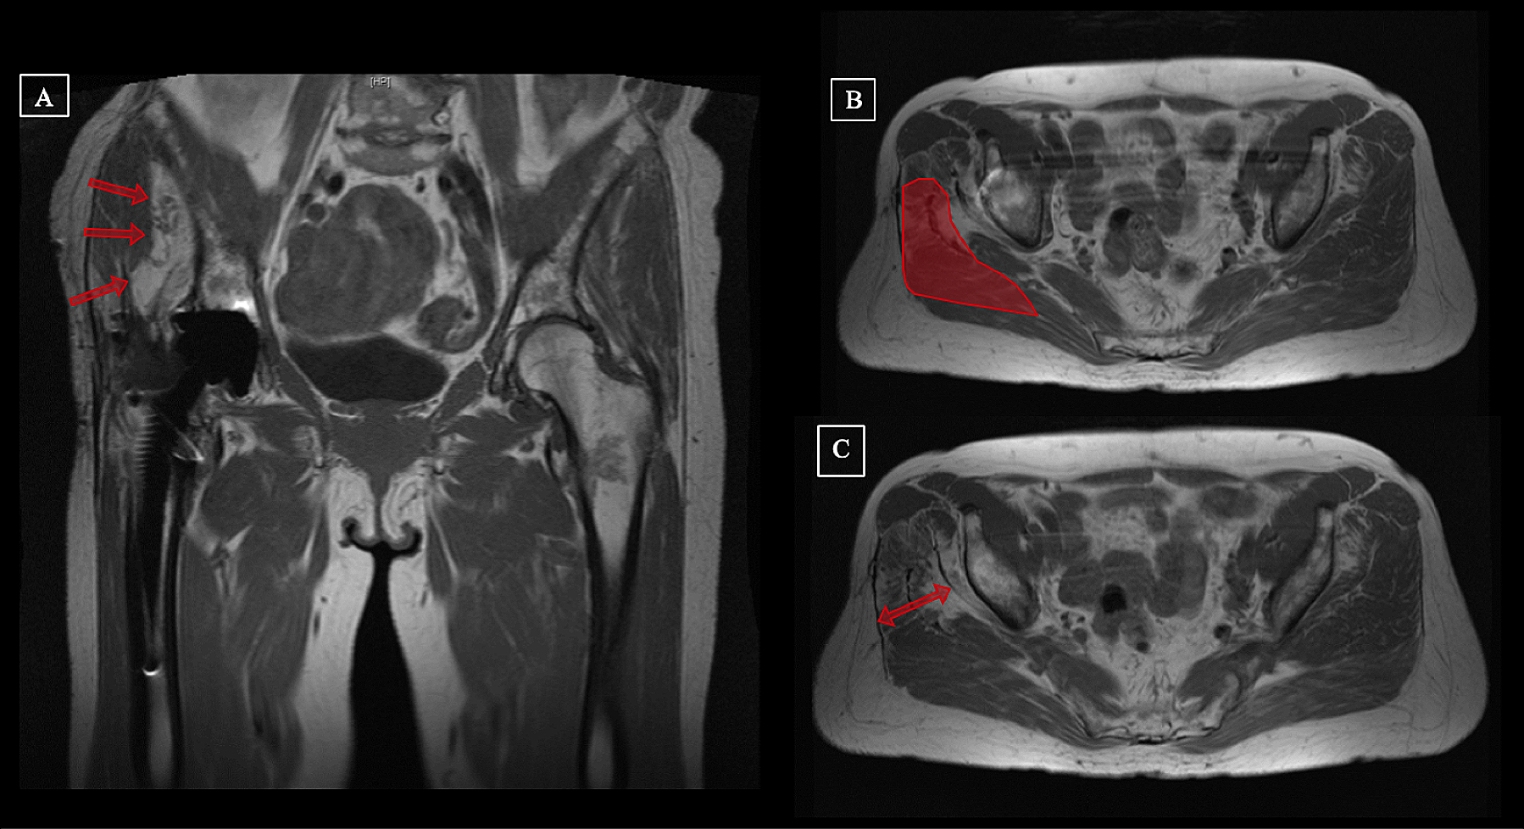

MRI scans were performed pre- and postoperatively. The total muscle volume, the volume of fatty degenerated muscular tissue, the lean muscle volume (total volume minus fat ratio) and the level of muscular degeneration after the Goutallier classification (G1-G4) were evaluated. All investigations were assessed by a musculoskeletal trained radiologist and an experienced orthopedic surgeon (K.T. and G.E.). Measurements were performed pre- and postoperatively for the following muscles: gluteus minimus (Gmin), gluteus medius (Gmed), gluteus maximus (Gmax) and tensor fascia lata muscle (TFL). The muscle flap size was included in the Gmax volume postoperatively (Fig. 1).

Fig. 1

Example and illustration of MRI measurements of the gluteal muscles. Preoperative (A and B) and postoperative (C and D) MR images after gluteus maximus flap transfer. Measurements regarding the level of degeneration (A and C, Goutallier IV) and the total muscle volume (B and D) of the gluteus medius muscle of a 64-year-old patient with chronic abductor mechanism deficiency on the right hip joint after total hip arthroplasty. To receive volumetric results, measurements were performed in slides of the MR image pre- and postoperatively and were highlighted for the gluteus medius muscle in this figure (B and D)